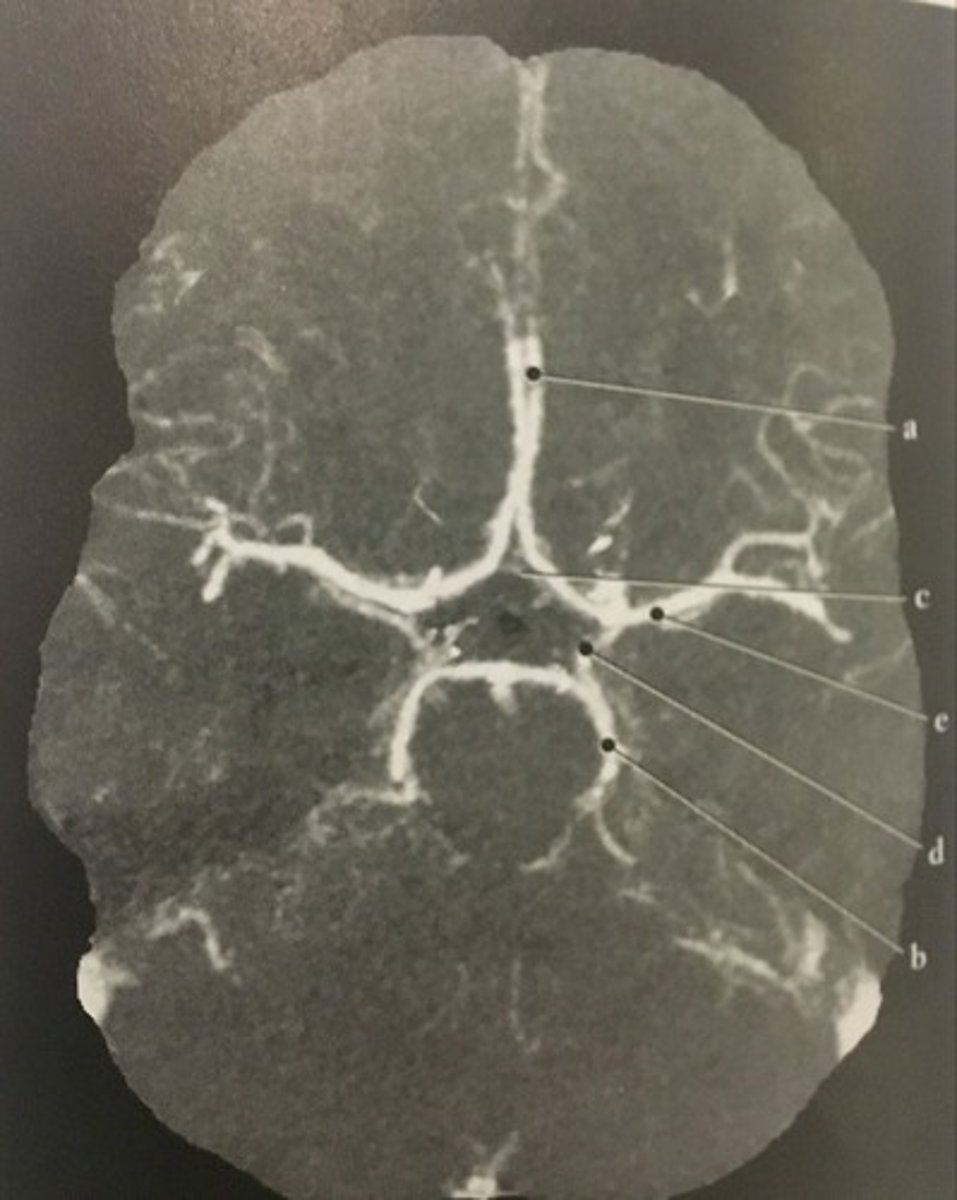

Anterior cerebral artery

<p>Identify structure A on this axial CTA of the Circle of Willis.</p>

Posterior cerebral artery

<p>Identify structure B on this axial CTA of the Circle of Willis.</p>

Anterior communicating artery

<p>Identify structure C on this axial CTA of the Circle of Willis.</p>

Posterior communicating artery

<p>Identify structure D on this axial CTA of the Circle of Willis.</p>

Middle cerebral artery

<p>Identify structure E on this axial CTA of the Circle of Willis.</p>